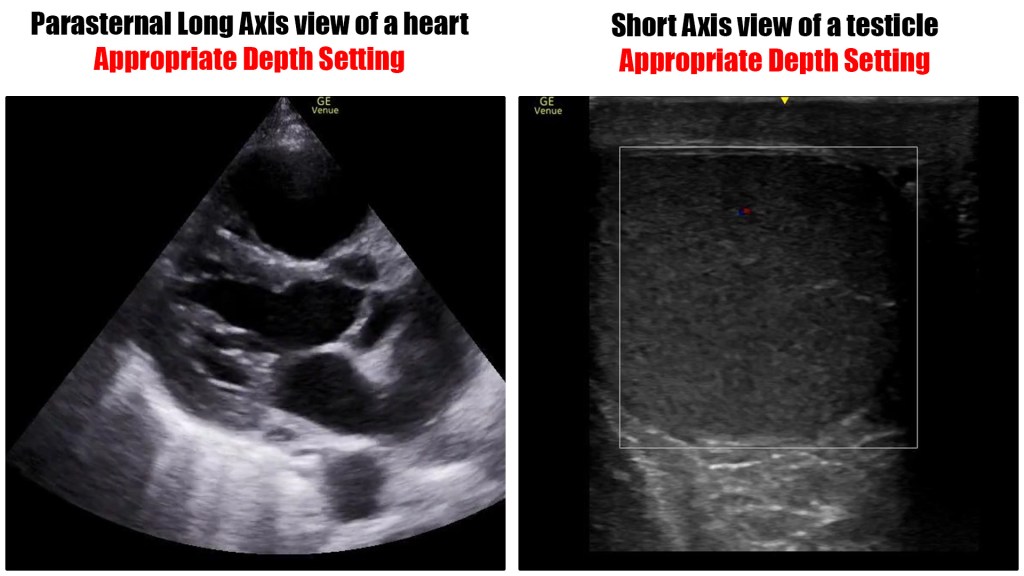

How do I get this right?

In general, it would be a good practice to set your depth such that the deepest edge of the AOI is about 3/4 of way down the image. That gives you a look at the entire organ in question and leaves some room at the deepest part of the image for context without “cutting it close.”

The cardiac preset is another one learners stumble though at times. The apical 4 chamber view almost always requires a different depth setting than the parasteranal views and subxiphoid view.